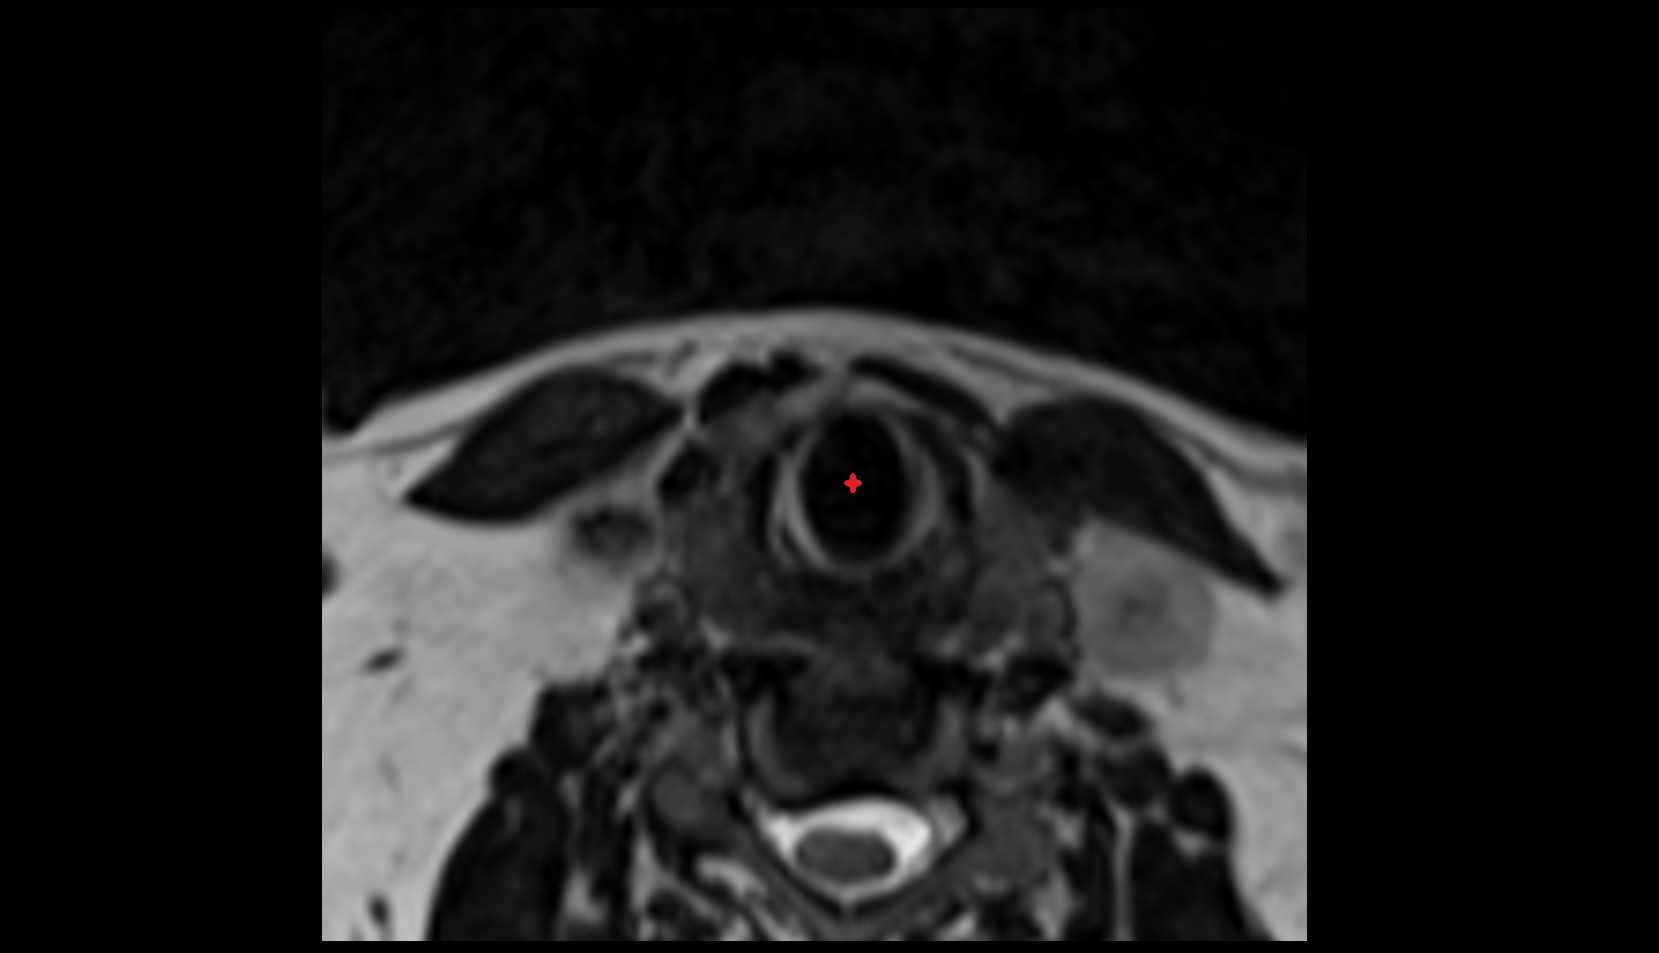

- Peripheral zone of prostate

- Anterior Fibromuscular Stroma of prostate

- Central zone of prostate

- Transitional zone of prostate